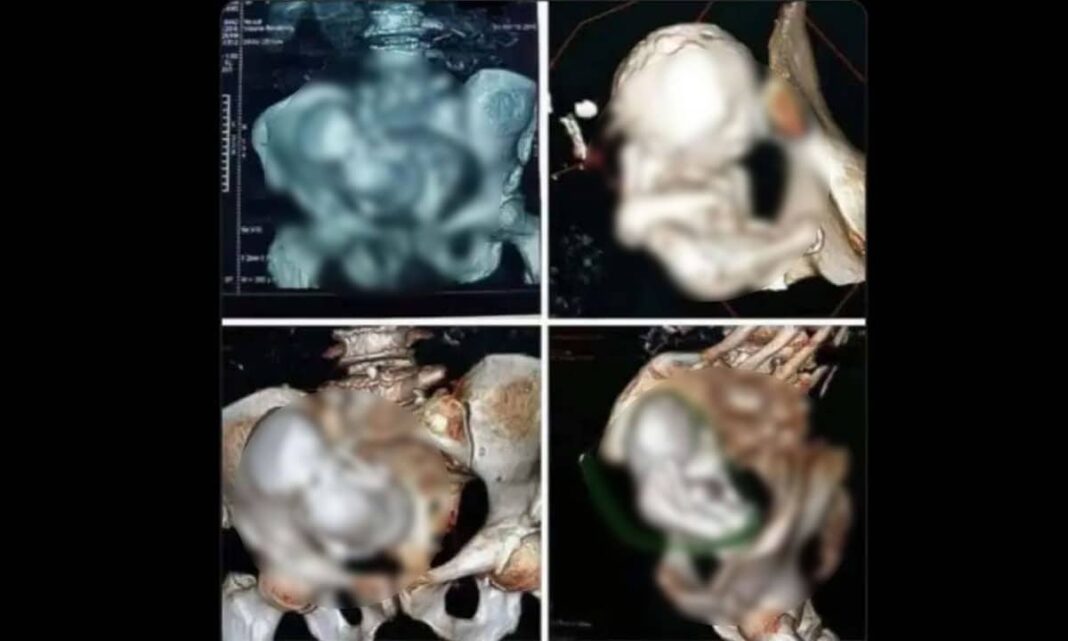

82 साल की इस महिला के शरीर में लगभग 4 पाउंड (करीब 1.8 किलो) का कैल्सिफाइड भ्रूण था, जिसे मेडिकल भाषा में लिथोपेडियन (Lithopedion) कहा जाता है। हैरानी की बात यह है कि महिला को इतने सालों तक इसका कोई पता नहीं चला। एक्स-रे करने पर डॉक्टरों को यह दुर्लभ स्थिति समझ आई। डॉक्टरों ने इसे ऑपरेशन करके इसे निकाल लिया है।

लिथोपेडियन बिना किसी लक्षण के हो सकता है, कई बार इसके लक्षण भी नजर आ सकते हैं जिन पर नजर रखनी जरूरी है। पेल्विस हिस्से में दर्द होना, पेट में भारीपन का अहसास, बड़े, कठोर द्रव्यमान के कारण के लक्षण। इस कंडीशन की पहचान अक्सर इमेजिंग तकनीकों जैसे कि प्लेन रेडियोग्राफी या कंप्यूटेड टोमोग्राफी (सीटी) स्कैन के जरिए की जाती है।